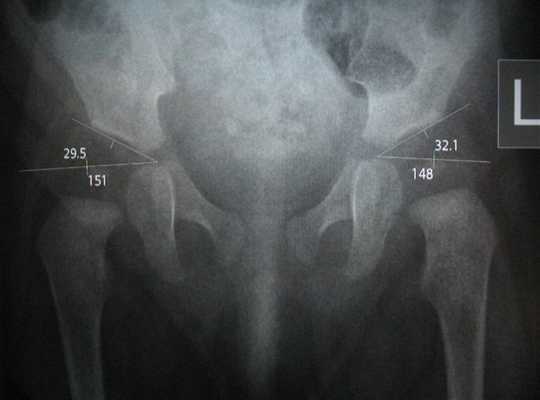

Следует иметь в виду, что рентген костей таза и тазобедренных суставов у детей раннего возраста не показывает точных очертаний суставных структур, так как их основная ткань — хрящевая, которую рентгеновские лучи не отображают. Поэтому интерпретацию полученной рентгенограммы — с определением смещения головки бедренной кости по отношению к вертлужной впадине тазовой кости — проводят с помощью накладывания на снимок специальной сетки, основные и вспомогательные линии которой соответствуют анатомически нормальному расположению структур сустава. Используя данные линии, измеряются различные параметры, в том числе центр вертлужной впадины и степень наклона ее крыши (ацетабулярный угол), угол отклонение шейки бедра вперед и т.д.

Учитывая угол Идельберга-Франка, угол Виберга и MZ-расстоянини децентрализации, статистическими методами можно выделить нормальные и патологические суставы: у взрослых значения тазобедренного сустава от 6 до 15 указывают на нормальную форму сустава; значения между 16 и 21 указывают на небольшую деформацию, а значения от 22 и выше указывают на серьезную деформацию, у детей значения от 15 и выше являются патологическими.

На рентгене признаки вывиха или дисплазии тазобедренных суставов визуализируются в виде вертикального и бокового смещений головки бедренной кости от вертлужной впадины тазовой кости (измеряемого на полученном снимке и сопоставляемого с анатомической нормой). Поверхность головки бедра часто не соответствует вертлужной впадине тазовой кости, например, при большом размере головки и недостаточной глубине впадины. А угол наклона плоскости входа в нее превышает норму.

Также отмечаются смещение центра вертлужной впадины, уменьшение или увеличение шеечно-диафизарного угла (определяемого между вертикальными осями шейки бедренной кости и ее телом — диафизом).

Еще один немаловажный рентген признак данной патологии — излишний наклон вперед узкой части бедренной кости (шейка бедра), который рентгенологи называют преувеличенной антеторсией.